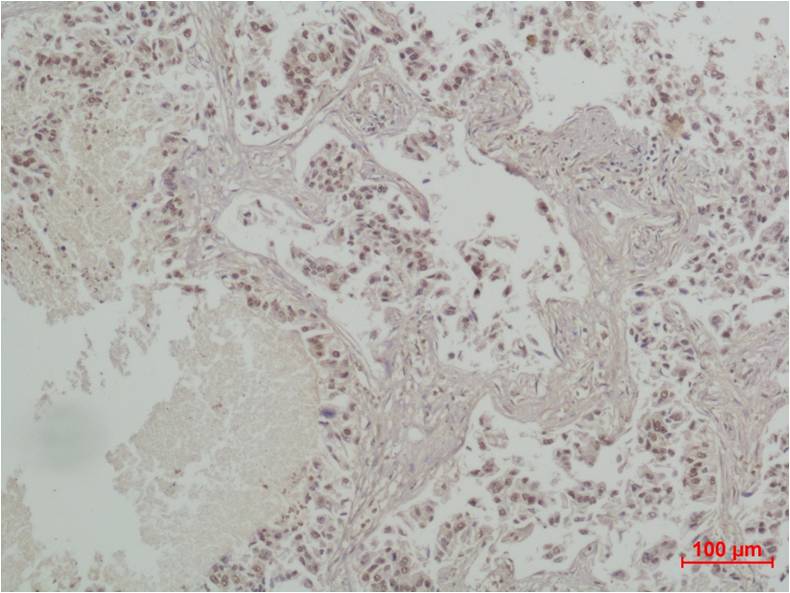

Product name: CREB Rabbit pAb

Dilutions: WB 1:1,000-2,000? IHC 1:200-500

Cellular localization: Nucleus

Background: CREB (cAMP response element-binding protein) is a cellular transcription factor. This protein binds the cAMP response element (CRE), a sequence present in many viral and cellular promoters. CREB is closely related in structure and function to CREM (cAMP response element modulator) and ATF-1 (activating transcription factor-1) proteins. CREB proteins are expressed in many animals.